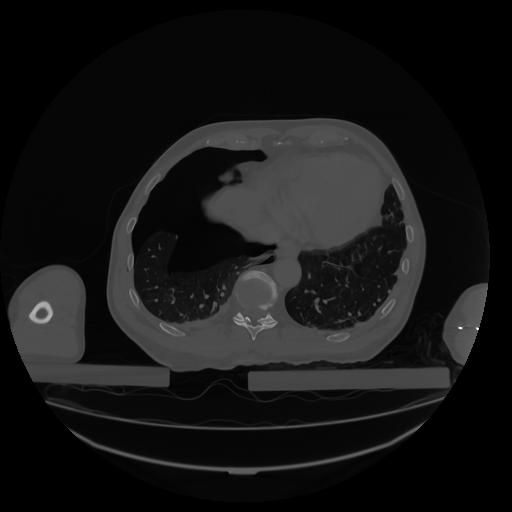

34 CUERPO,CE,Vol,1.0,CUERPO,,